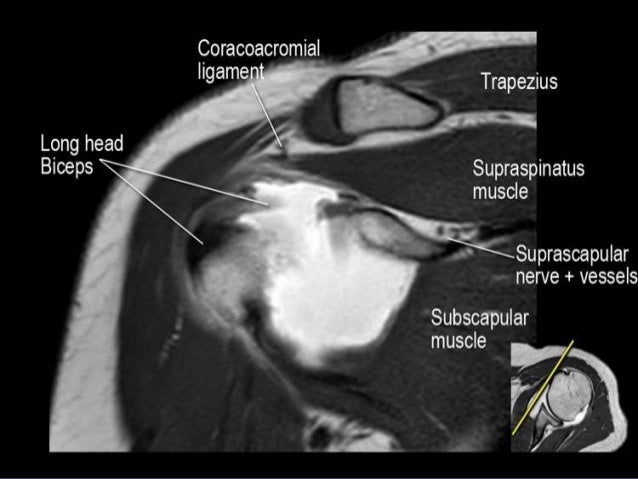

Mri of shoulder anatomy dr. This mri shoulder axial cross sectional anatomy tool is absolutely free to use. An mri of the shoulder of a healthy subject was performed in the 3 planes of space coronal axial sagittal commonly used in osteoarticular imagery with two weightings most commonly used to explore the musculo skeletal pathology of the shoulder.

Use the mouse scroll wheel to move the images up and down alternatively use the tiny arrows on both side of the image to move the images on both side of the image to move the images. Use the mouse to scroll or the arrows. This webpage presents the anatomical structures found on shoulder mri.